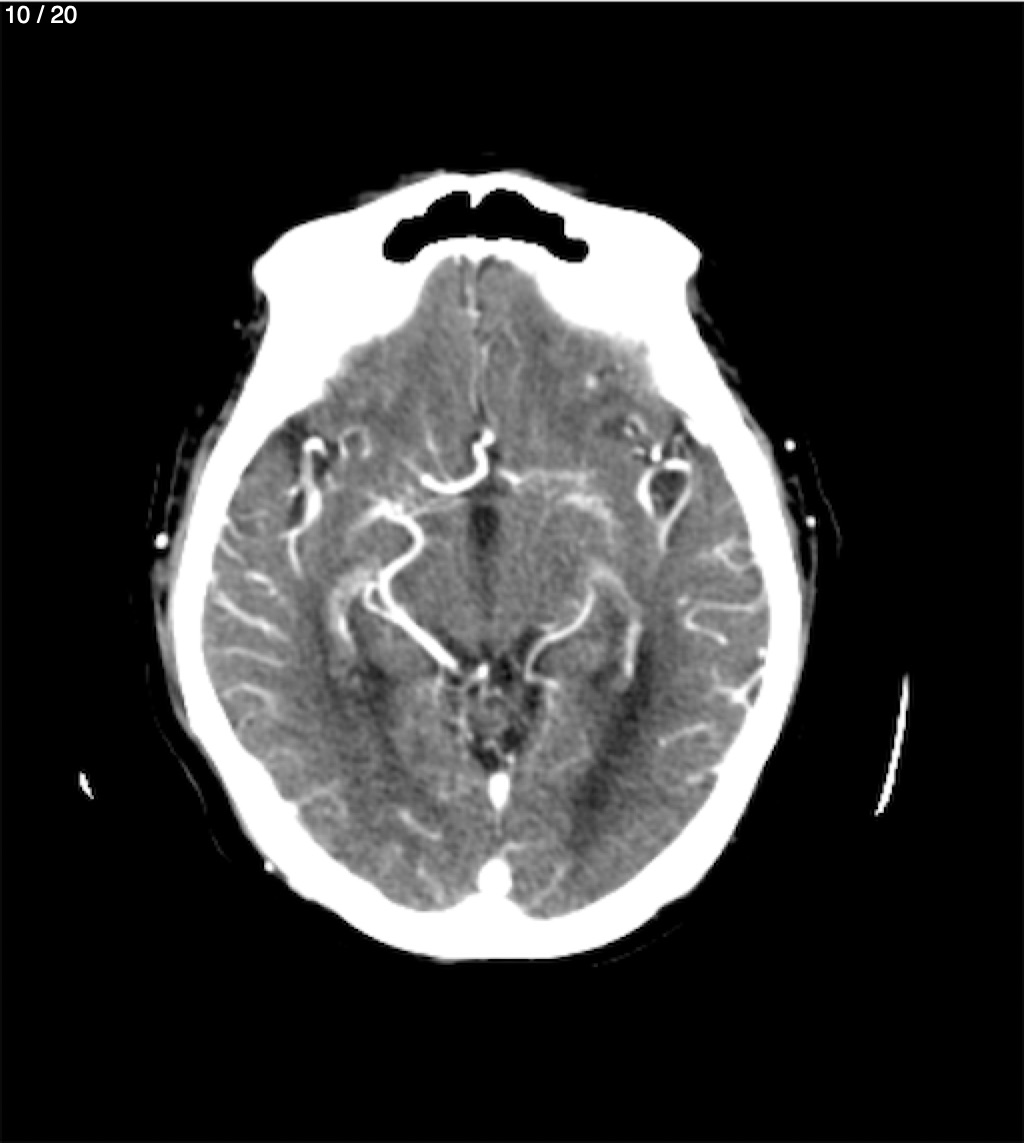

Jose Sosa Martinez 66A - Angiotac Craneo